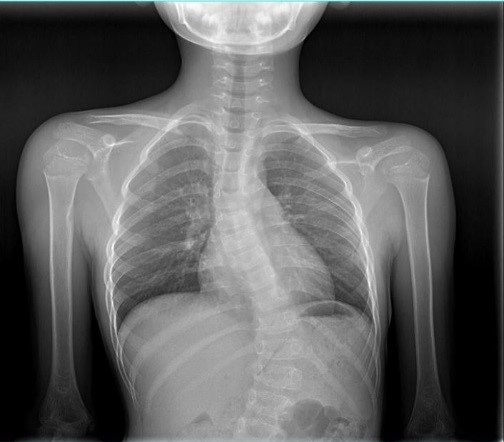

男 15岁

脊柱侧弯畸形

AEC 80KV

脊柱侧弯畸矫形术前检查

通过全景拼接图像可以清晰显示脊柱侧弯的具体细节,为矫形手术提供更详尽的资料。